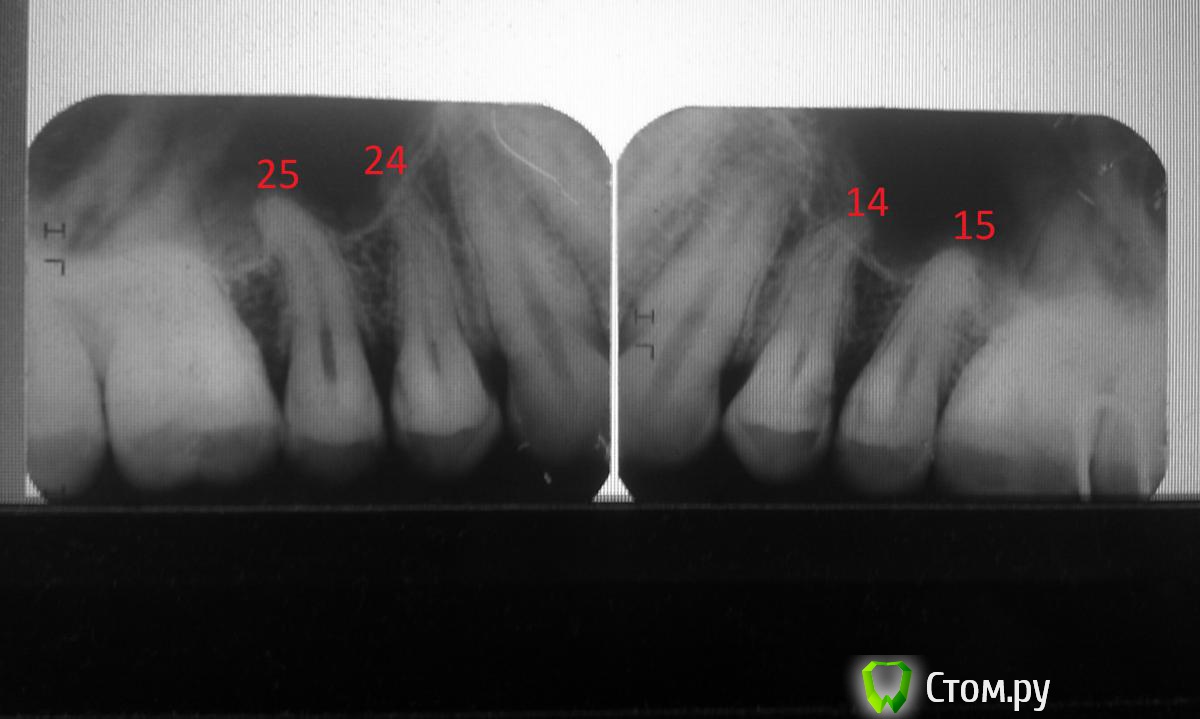

alphavir Опубликовано 3 января, 2014 Поделиться Опубликовано 3 января, 2014 Здравствуйте! Помогите разобраться со снимками. На двух снимках 25, 24 и 14,15 зубы соответственно. На 14 зубе видна глубокая кариозная область. Это пульпит или глубокий кариес? Если это глубокий кариес, то можно ли сохранить нерв? Также прошу прокомментировать 25, 24 и 15 зуб. Там тоже есть кариес, но какой, глубокий или средний? Ни один зуб при этом не болит, не беспокоит, на холодное/горячее не реагирует. Ссылка на комментарий

Kolchanov Опубликовано 3 января, 2014 Поделиться Опубликовано 3 января, 2014 Это пульпит или глубокий кариес? Это выяснится после обследования и удаления нежизнеспособных тканей зуба. Если будет сообщение с полостью зуба, то придется удалять пульпу. Думаю обойдется На 15 тоже полость, кажись, есть. Ссылка на комментарий